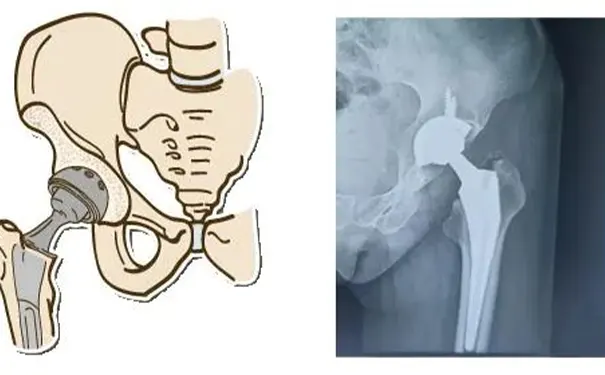

髋关节置换术:若股骨头已崩塌、关节面受损,引发严重髋关节炎,需移除坏死的股骨头及软骨,置入人工关节以恢复关节功能。